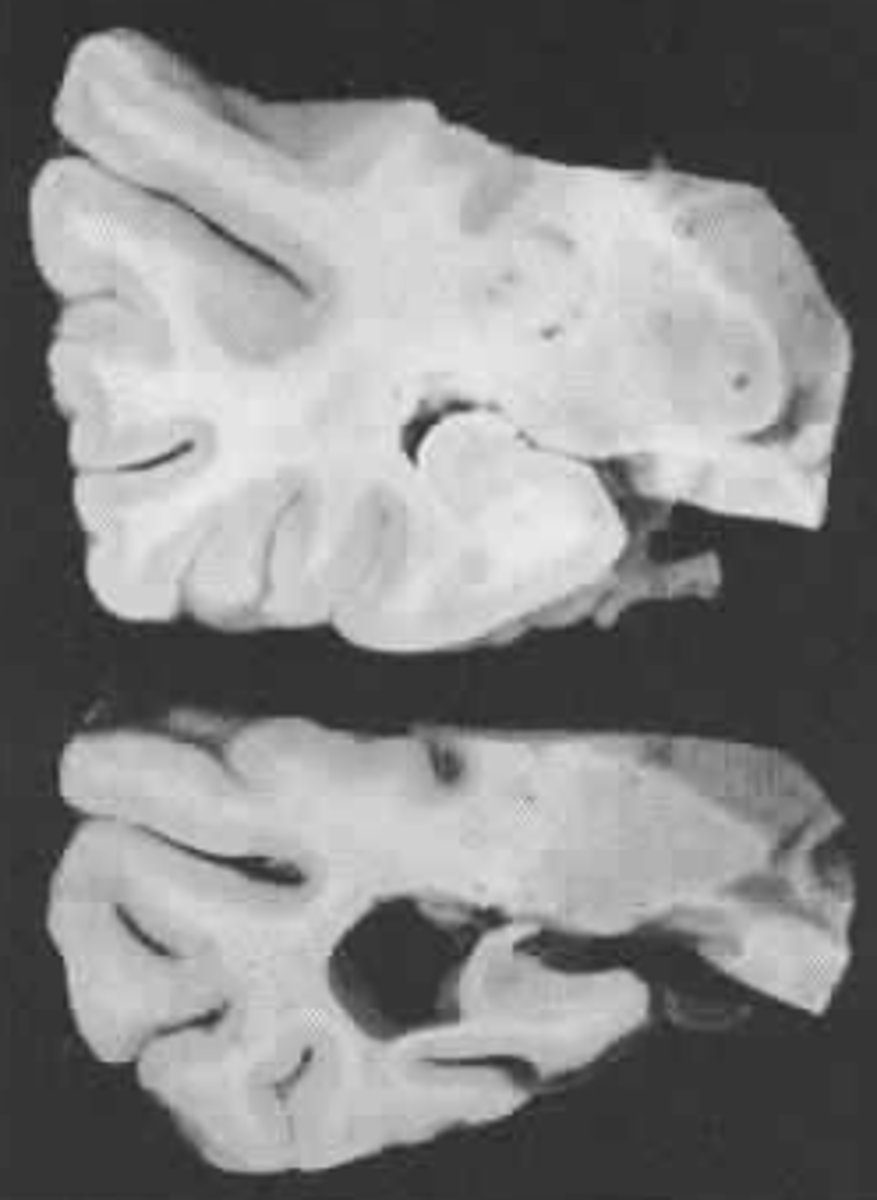

What is the etiology of Huntington's Disease?

Loss of cells in the striatum (cortex and basal ganglia)

What is the hallmark symptom of Huntington's Disease?

Involuntary movement

Signs and Symptoms of Huntington's Disease

Changes in personality

Alterations in mood

Decline in cognitive functions